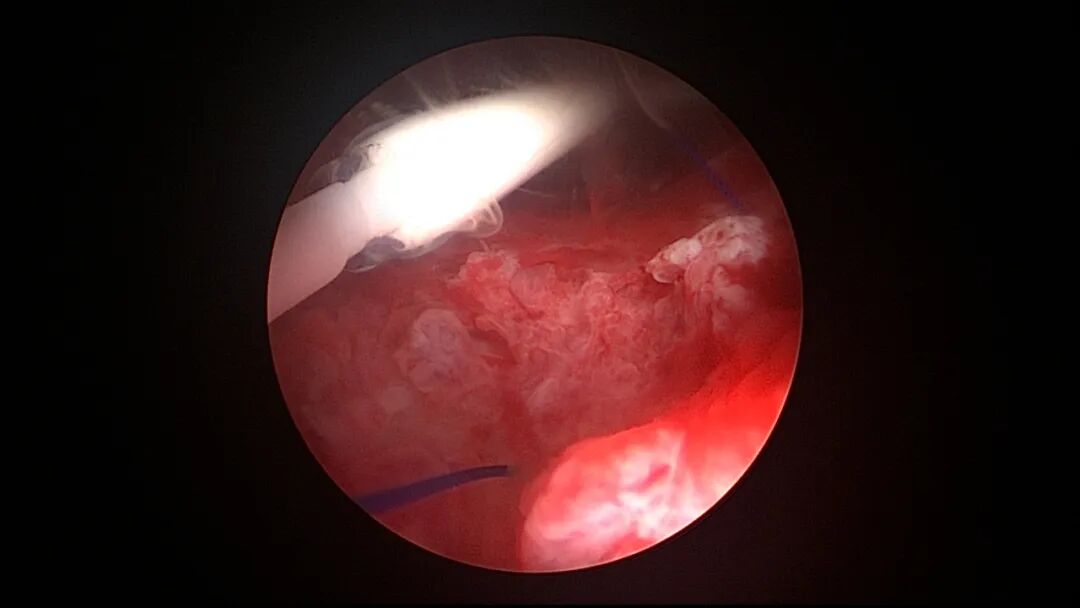

取胚术后丝线挂钩固定节育环图片及视频

子宫腺肌症内膜息肉切除后丝线挂钩固定曼月乐并电凝图片及视频

异常子宫出血内膜增生节育环尾丝挂钩固定曼月乐图片及视频

挂钩固定注意事项:月经干净3~7天手术,此时内膜最薄,利于挂钩固定到子宫肌层,如果内膜较厚,最好用负压吸引器去除内膜,暴露基底层,挂钩才能放置到位,也避免内膜掀起、出血等影响操作。挂钩尖端能轻松在子宫壁上粘附,然后调整钳的位置,将挂钩插入到宫底肌层。也可以在体外连接好挂钩和节育环,同时送入宫腔,异物钳在宫腔夹持挂钩并插入宫底肌层。术后复查B超节育环距宫底距离可能较大,个别达3cm左右,跟子宫大、宫壁厚、外加挂钩长度及线圈长度之和较大有关,保持这个距离不再延长即为手术成功。